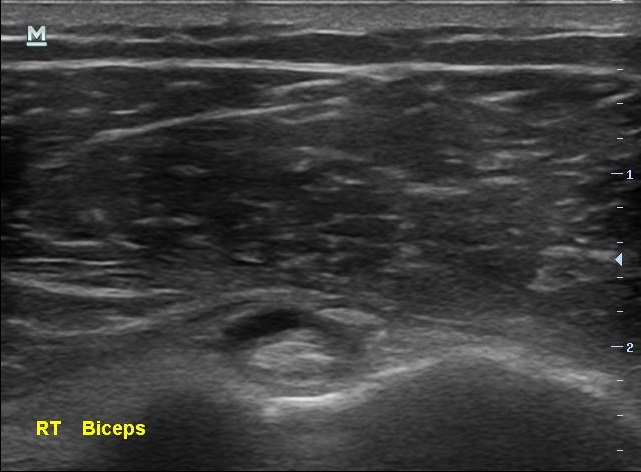

박상준 의원 병원위치, 진료시간, 연락처 등등이 궁금하면 클릭하세요. ^^ (당산 당산역 여의도 합정 목동 영등포 영등포구청 선유도 양평동 국회의사당 정형외과 야간진료 도수치료 통증의학과 박상준의원) 안녕하세요 당산 박상준 의원의 박상준 원장입니다. 오늘은 종아리 통증으로 오래 고생했던 환자 이야기를 해볼까 합니다. 며칠전 젊은 트레이너 여성분이 병원에 찾아왔습니다. 나 : 어디가 불편해서 오셨어요? 여성 : 종아리가 아파요 ㅜㅜ 나 : 아픈지 얼마나 되었나요? 여성 : 음.... 그러니까...... 10년은 된거 같네요... 나 : 네? ^^;;;; 트레이너라는 직업특성상 운동을 많이 하는 이 여성, 운동을 많이 하니 종아리가 피곤하고 아플 수 있겠죠ㅕ... 그런데 아픈게 10년이 넘었다고 합니다. 나..